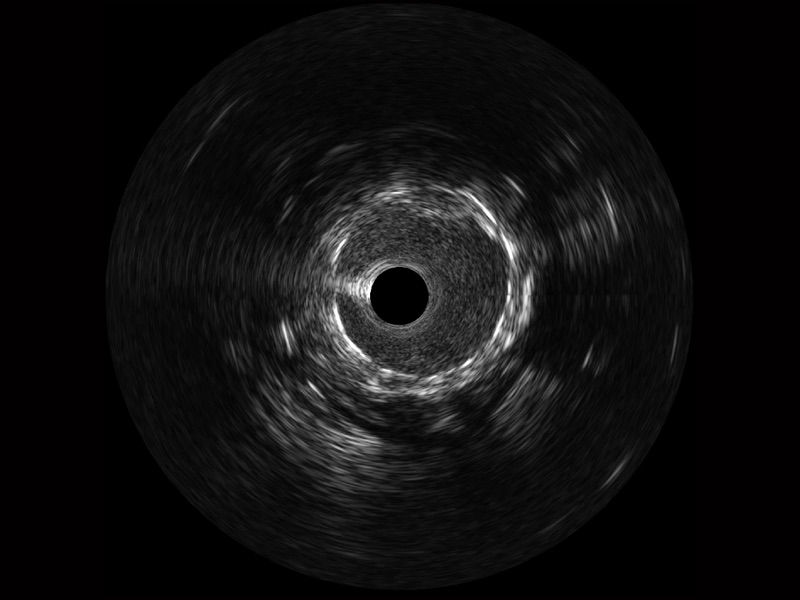

治疗前后两次测量录像对比

简化疗效评估

一键智能描迹,自动测量斑块负荷、面积狭窄率等指标,准确率高于90%